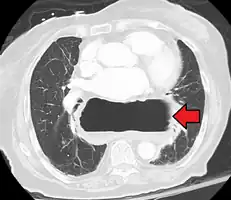

A hiatal hernia as seen on CT

A large hiatal hernia as seen on CT imaging